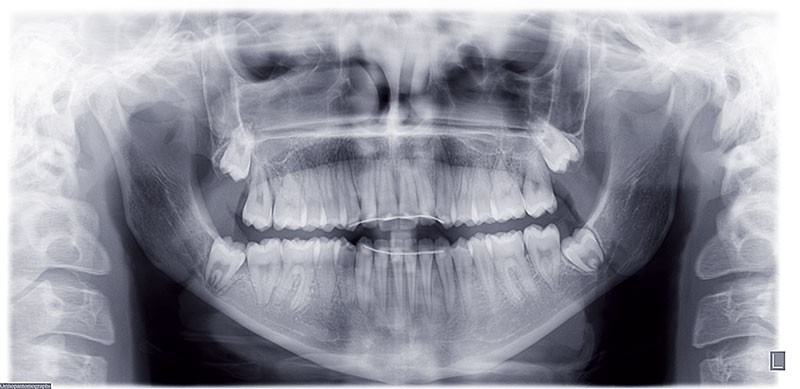

Nous sommes en présence d’une patiente en fin de croissance faciale, âgée de 16 ans. Elle présente une classe III dentaire et squelettique associée à une asymétrie faciale de type latérognathie mandibulaire avec déviation des points interincisifs et déviation du menton vers la gauche.